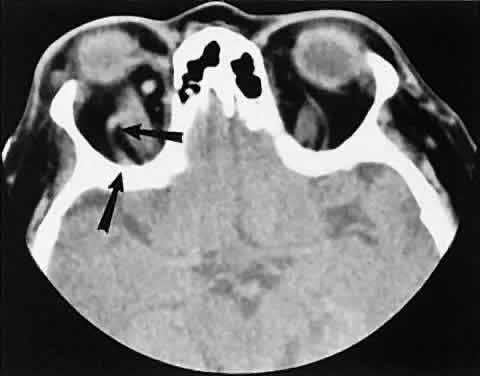

Graves' orbitopathy probably represents the most frequent cause of proptosis and EOM enlargement. The CT findings are fairly stereotyped and typically display various degrees of EOM enlargement (Fig. 7). The inferior rectus muscle usually is affected earliest, followed by the medial rectus, superior rectus, and finally the lateral rectus muscle. Rootman and colleagues13 noted more frequent involvement of the superior rectus/levator and medial rectus muscles than what had been reported previously with Graves' orbitopathy. These muscles can be affected in isolation, with the exception of the lateral rectus. To the best of our knowledge, isolated lateral rectus enlargement has not been reported in Graves' orbitopathy and in our experience usually is associated with a sphenoid wing meningioma.

Fig. 7. Graves' orbitopathy with two variations. Axial (A) and coronal (B) views show symmetric fusiform enlargement of the extraocular muscles with tapered muscle insertions. Note the predominant enlargement of the inferior, medial, and superior rectus muscles with lesser involvement of the lateral rectus muscle, a frequent pattern of enlargement in Graves' orbitopathy. Axial (C) and coronal (D) views of Graves' orbitopathy with expansion of retrobulbar ground substance and relative sparing of the extraocular muscles.

CT evidence of Graves' orbitopathy tends to be bilateral. Approximately 86% of patients with unilateral clinical findings have bilateral CT findings in our experience, which is consistent with the experience of others.42

Morphologically, the EOM belly is enlarged, with a gradual tapering toward and sparing of the tendinous portion of the muscle. Tendon involvement is a typical feature of orbital myositis. Tendon involvement helps to differentiate this lesion from Graves' orbitopathy, although Rootman and Nugent43 have noted a rare patient with Graves' orbitopathy with this finding.